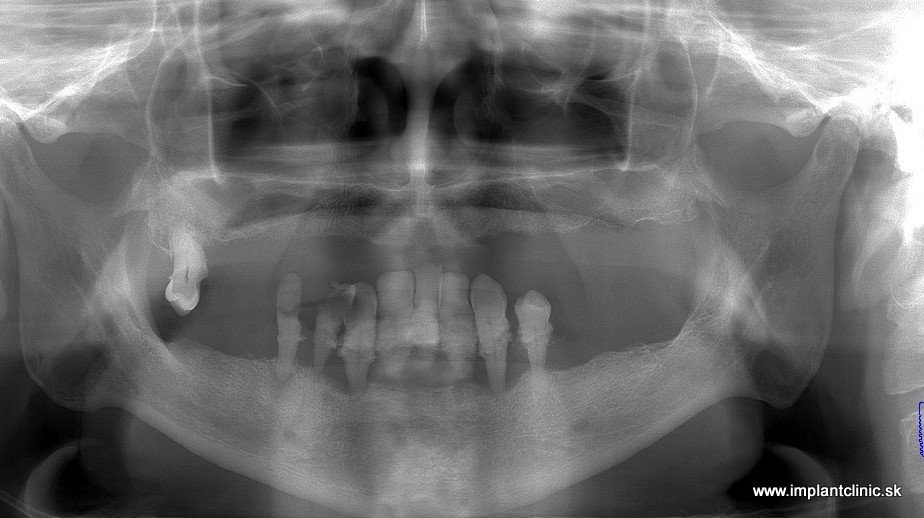

Komplexné ošetrenie bolo potrebné aj u nášho pacienta Ladislava. Nemal žiadne zuby vo vrchnej čeľusti a v sánke mu zostalo už len málo nefunkčných zubov.

Plán ošetrenia pána Ladislava: 6 zubných implantátov v čeľusti a aj v sánke, dostavba kosti, 14 – členný keramický mostík v oboch čeľustiach.

Snímka pred ošetrením